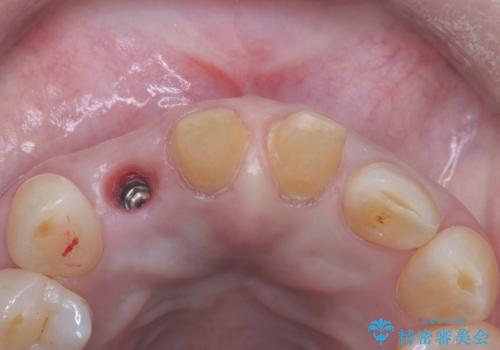

インプラント治療は、低侵襲で短期間に行える「抜歯即時インプラント治療」を選択しました。

この方法は、抜歯したその日にインプラントを埋入し、手術が1回で済むのが大きな特徴です。

また、オペ当日には仮歯まで装着するため、見た目を気にせず普段通りの生活を送ることができます。